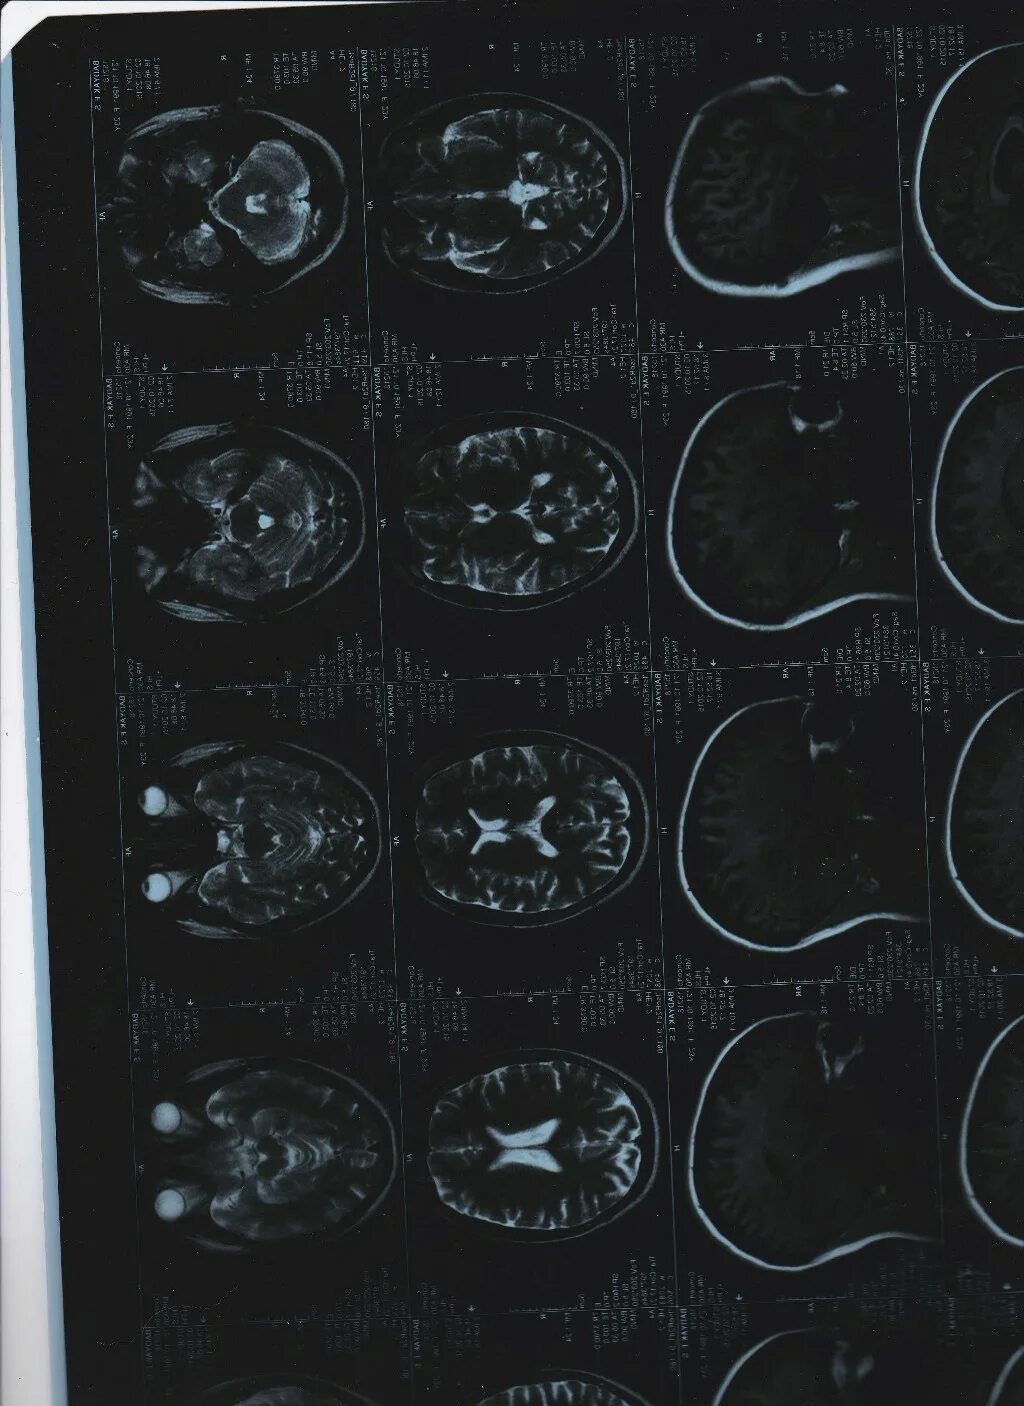

Давление изнутри головы